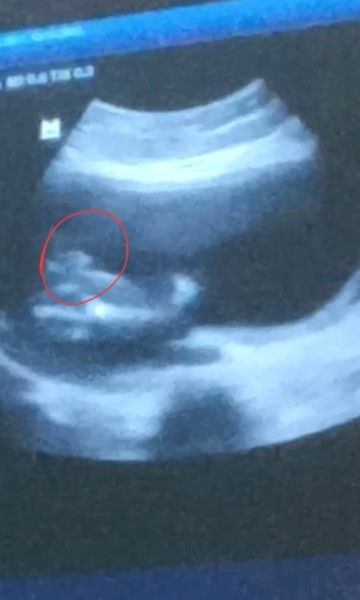

HALLO BUN!!! Saya USG 18 week, awalnya terlihat cowok tapi setelah dilihat lagi dokternya yakin cewek USG lagi 20 week, awalnya dilihat cewe tapi ternyata kok dilihat2 lagi ada pistolnya. Untuk lebih yakin bulan depan disuruh usg lagi 2 kali usg JK dokternya masih belum yakin, dan hasil screenshoot vidio terakhir seperti ini. Jadi ini cewek atau cowok ya bund kira2??😁 Cewek cowok yang penting sehat cuma penasaran saja maklum anak pertama cucu pertama banyak yg nanyain #bantusharing #seriusnanya